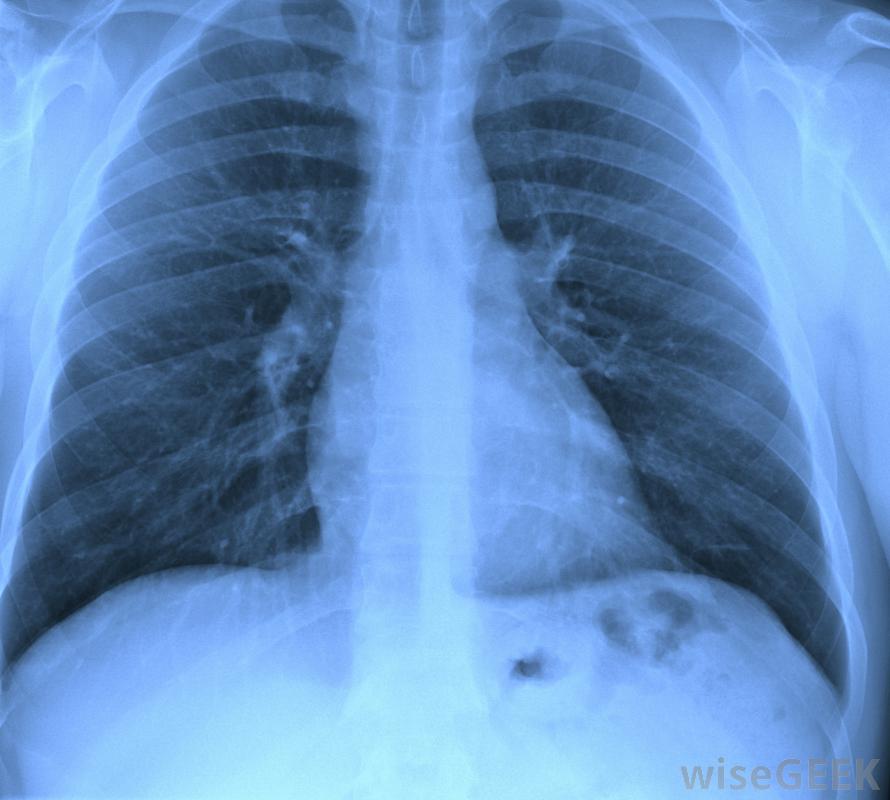

肺結核有什么癥狀(Symptoms of Tuberculosis)?

結核病是一種常見的疾病,世界上約三分之一的人口曾接觸過結核病,但大多數人仍然沒有癥狀。患有活動性結核病感染的人往往會出現典型的癥狀和體征。肺結核的癥狀通常包括慢性咳嗽,可能會產生血性痰,胸痛、體重減輕和發燒。慢性咳嗽可能是肺結核的征兆。在人類中,肺結核是由結核分枝桿菌引起的,結核分枝桿菌是一種感染肺部的細菌。根據胸部x光片、皮膚測試和痰檢,確診為肺結核,肺結核患者的痰中含有細菌,痰是從下呼吸道和呼吸道咳出的物質,含有粘液、唾液和任何感染下呼吸道和肺部的細菌肺結核是由一種感染肺部的細菌引起的。通常根據肺結核的癥狀進行初步診斷肺結核最常見的癥狀和體征包括慢性咳嗽、痰中帶血、盜汗和發燒、胸痛和不明原因的體重減輕有這些癥狀的人通常會被轉診進行胸部x光片、痰檢和其他檢查,以確認肺結核的診斷。皮膚測試通常是結核病診斷的一部分肺結核的癥狀是由結核分枝桿菌感染的結果。當細菌開始在肺泡內定植時,開始感染。一旦定植開始,細菌被稱為巨噬細胞的免疫細胞攝取,巨噬細胞是一種負責攝取和分解細菌細胞和細胞碎片的細胞類型。巨噬細胞通常不難消化細菌;但是,它們無法殺死它們攝入的結核分枝桿菌醫學專業人員可能會檢查胸部X光片,以確定是否有結核病的跡象。隨著感染的進展,其他免疫細胞,包括T細胞和B細胞,開始聚集在受感染的巨噬細胞周圍。免疫細胞形成團塊,稱為肉芽腫,是被T淋巴細胞和B淋巴細胞包圍的受感染巨噬細胞的小區域。當免疫細胞無法消除感染時,免疫系統會形成肉芽腫,而不是殺死病原體,在肉芽腫中,淋巴細胞分泌細胞因子,幫助殺死入侵的細菌肺結核的典型癥狀,包括血性痰、咳嗽和發燒,都是由這種慢性感染引起的。感染模式可能包括肉芽腫形成、組織破壞和愈合的多個周期,如果不治療,可能會持續數年甚至數十年。隨著感染的發展,肺組織逐漸變得傷痕累累,降低了受感染者的肺功能。隨著疾病的發展,受感染者也變得更具傳染性,因為當他們的肺組織變得更壞死時,他們更有可能咳出受感染的物質肺結核的癥狀和體征可能包括發燒、腹痛和疲勞。